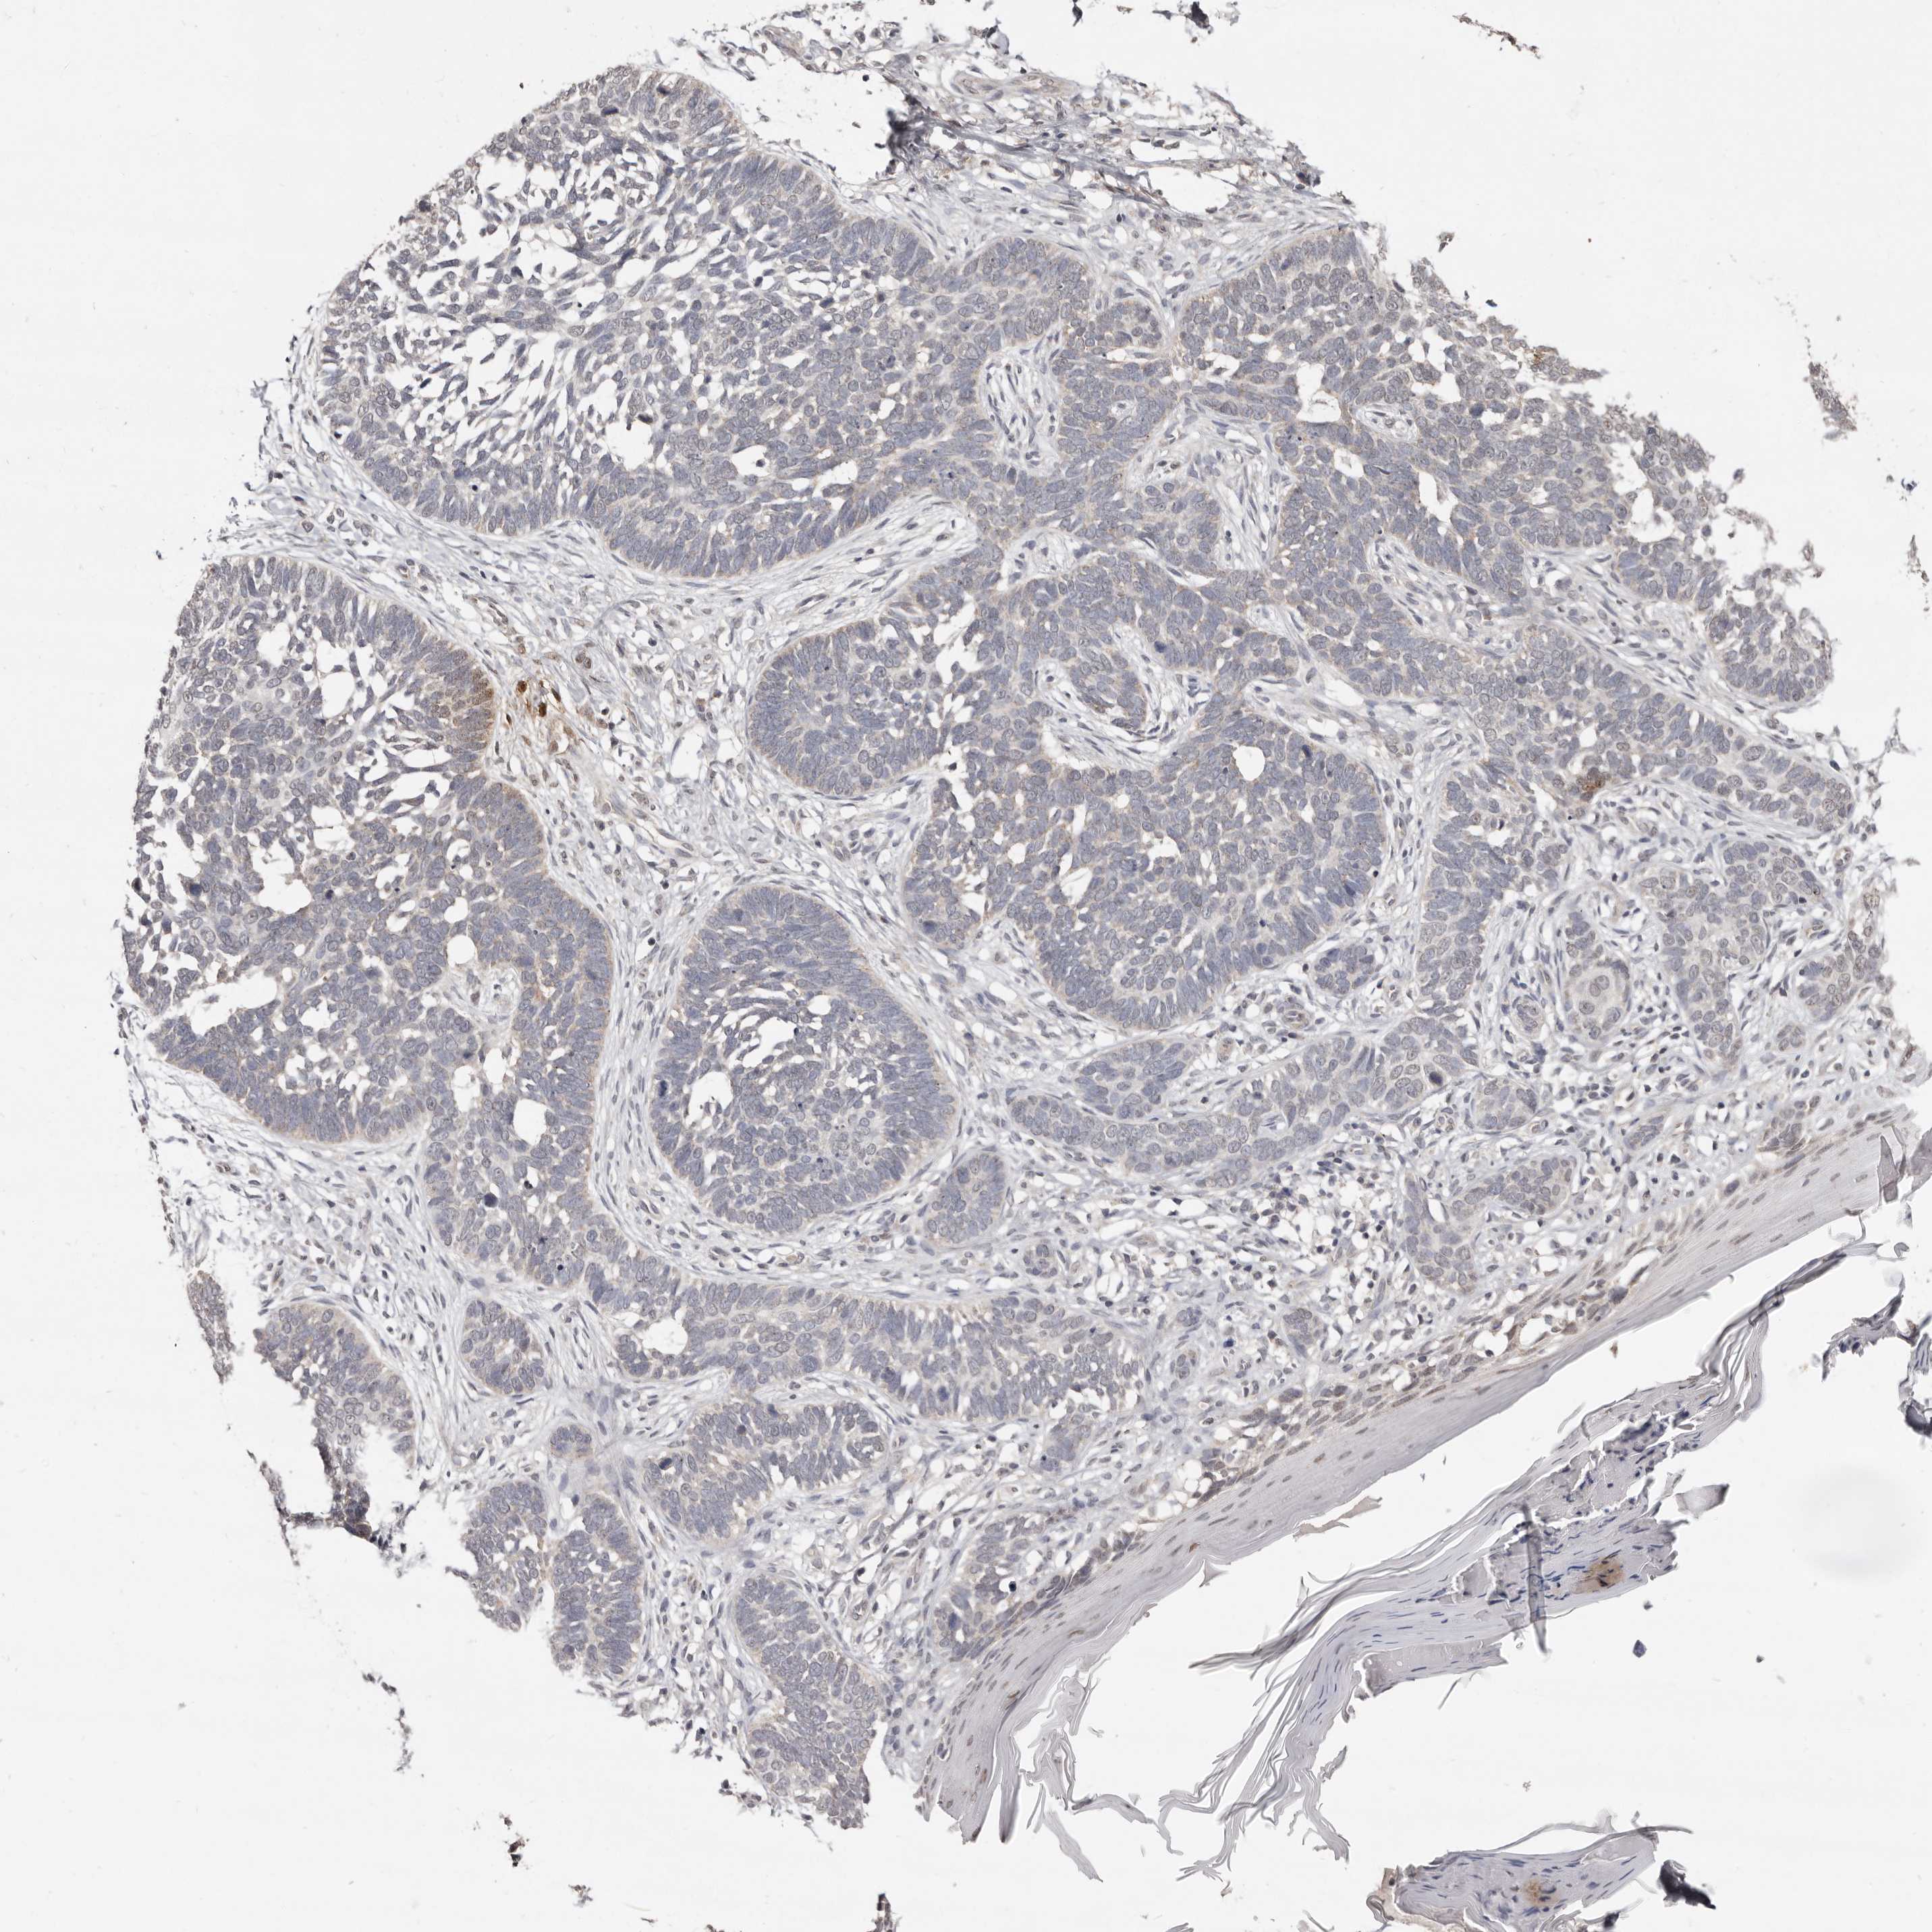

SKIN CANCER - Protein expressioni

A mouse-over function shows sample information and annotation data. Click on an image to view it in a full screen mode. Samples can be filtered based on level of antibody staining by selecting one or several of the following categories: high, medium, low and not detected. The assay and annotation is described here.

Antibody stainingi

Antibody staining in the annotated cell types in the current human tissue is reported as not detected, low, medium, or high, based on conventional immunohistochemistry profiling in selected tissues. This score is based on the combination of the staining intensity and fraction of stained cells.

Each image is clickable and will lead to virtual microscopy that enables deeper exploration of all samples and also displays staining intensity scores, fraction scores and subcellular localization as well as patient and tissue information for each sample.

Antibody HPA016633

Squamous cell carcinoma in situ, NOS